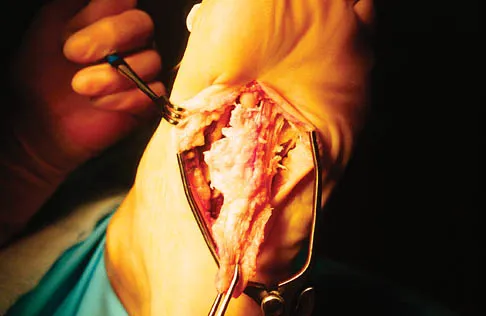

Question 31

A 56-year-old woman has a painful mass on the bottom of her left foot, and orthotic management has failed to provide relief. Examination reveals that the mass is contiguous with the plantar fascia. An MRI scan shows a homogenous nodule within the plantar fascia. Resection of the tumor is shown in the clinical photograph in Figure 39. What type of cell is most likely responsible for the formation of this tumor?

Explanation